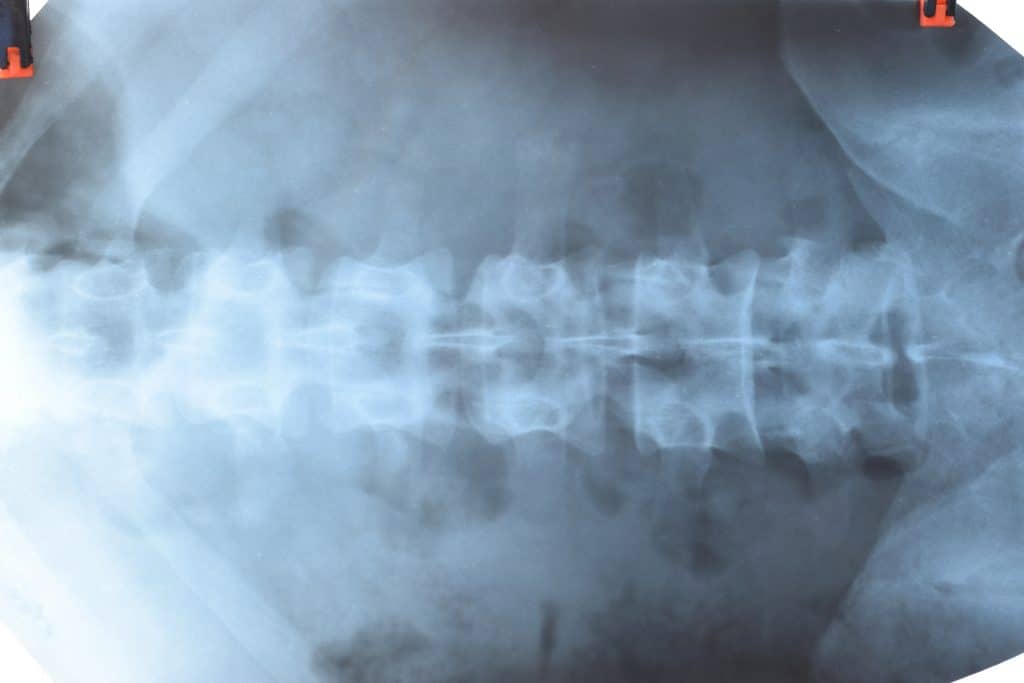

Radi navedenih simptoma, poželjno je da se stanje što prije prepoznaje i liječi. Pravilna dijagnoza navedenog stanja će se utvrditi uz pomoć obiteljskog liječnika, radiologa, imunologa, reumatologa, fizijatra, fizioterapeuta. Dijagnoza će se postaviti uz pomoć kliničke slike osobe, rendgena i magnete rezonancije kralježnice, krvnih pretraga, određivanje HLA antigena. Bechterewljeva bolest se može i ne mora liječiti cijeli život, a to će ovisiti o težini samih simptoma. Kada se uspostavi da osoba boluje od navedene bolesti, bitno je da ona shvati svoje stanje i da ostane svakodnevno aktivna.